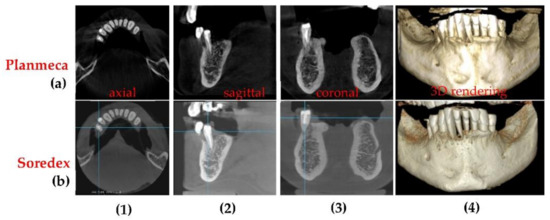

3.4. Differences Between the Planmeca and the Soredex System

| Radiograph | Characteristics | Planmeca | Soredex | |

|---|---|---|---|---|

| Panoramic | Anode voltage (kV) | 68 to 73 | 70 to 75 | |

| Current intensity (mA) | 8 to 11 | 8 to 11 | ||

| Exposure time (s) | 14.990 | 16 | ||

| DAP (mGy×cm2) | 97 to 117 | 175 to 250 | ||

| Effective Dose (µSv) | 7.8 to 9.2 | 14 to 20 | ||

| Pixel side (µm) | 127 | 100 | ||

| Total 3D CBCT | Anode voltage (kV) | 90 | 85 to 90 | |

| Current intensity (mA) | 11 to 14 | 6 to 10 | ||

| Exposure time (s) | 5 | 6 to 9 | ||

| DAP (mGy×cm2) | 691* | 749.5 ** | ||

| Effective Dose (µSv) | 86.4* | 93.7 ** | ||

| Voxel side (µm) | 150 | 200 | ||

| Base diameter (mm) | of the investigated volume | 110 | 150 | |

| Height (mm) | 80 | 80 | ||

| Panoramic | Planmeca and Soredex | Radiation dose is almost 50% smaller for Planmeca. Resolution is lower (127 µm) for Planmeca than for Soredex (100 µm). Images produced by Soredex have a lower contrast and sharpness even if they have better resolutions. |

| 3D CBCT | Planmeca and Soredex | Smaller exposure time (5 versus 9 s), smaller radiation dose (with at least 10 µSv), and smaller voxel side (with 25%) for Planmeca, which means better resolution, contrast, and image quality. The covered volume is larger for Soredex. |